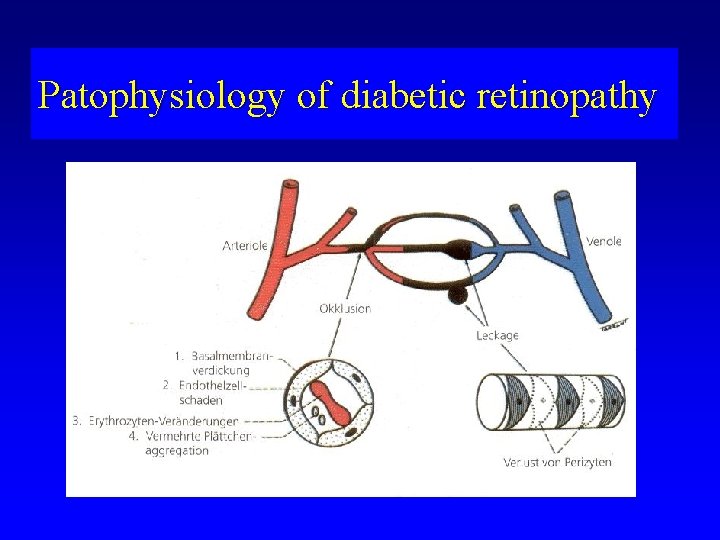

Patophysiology of diabetic retinopathy

Patophysiology of diabetic retinopathy